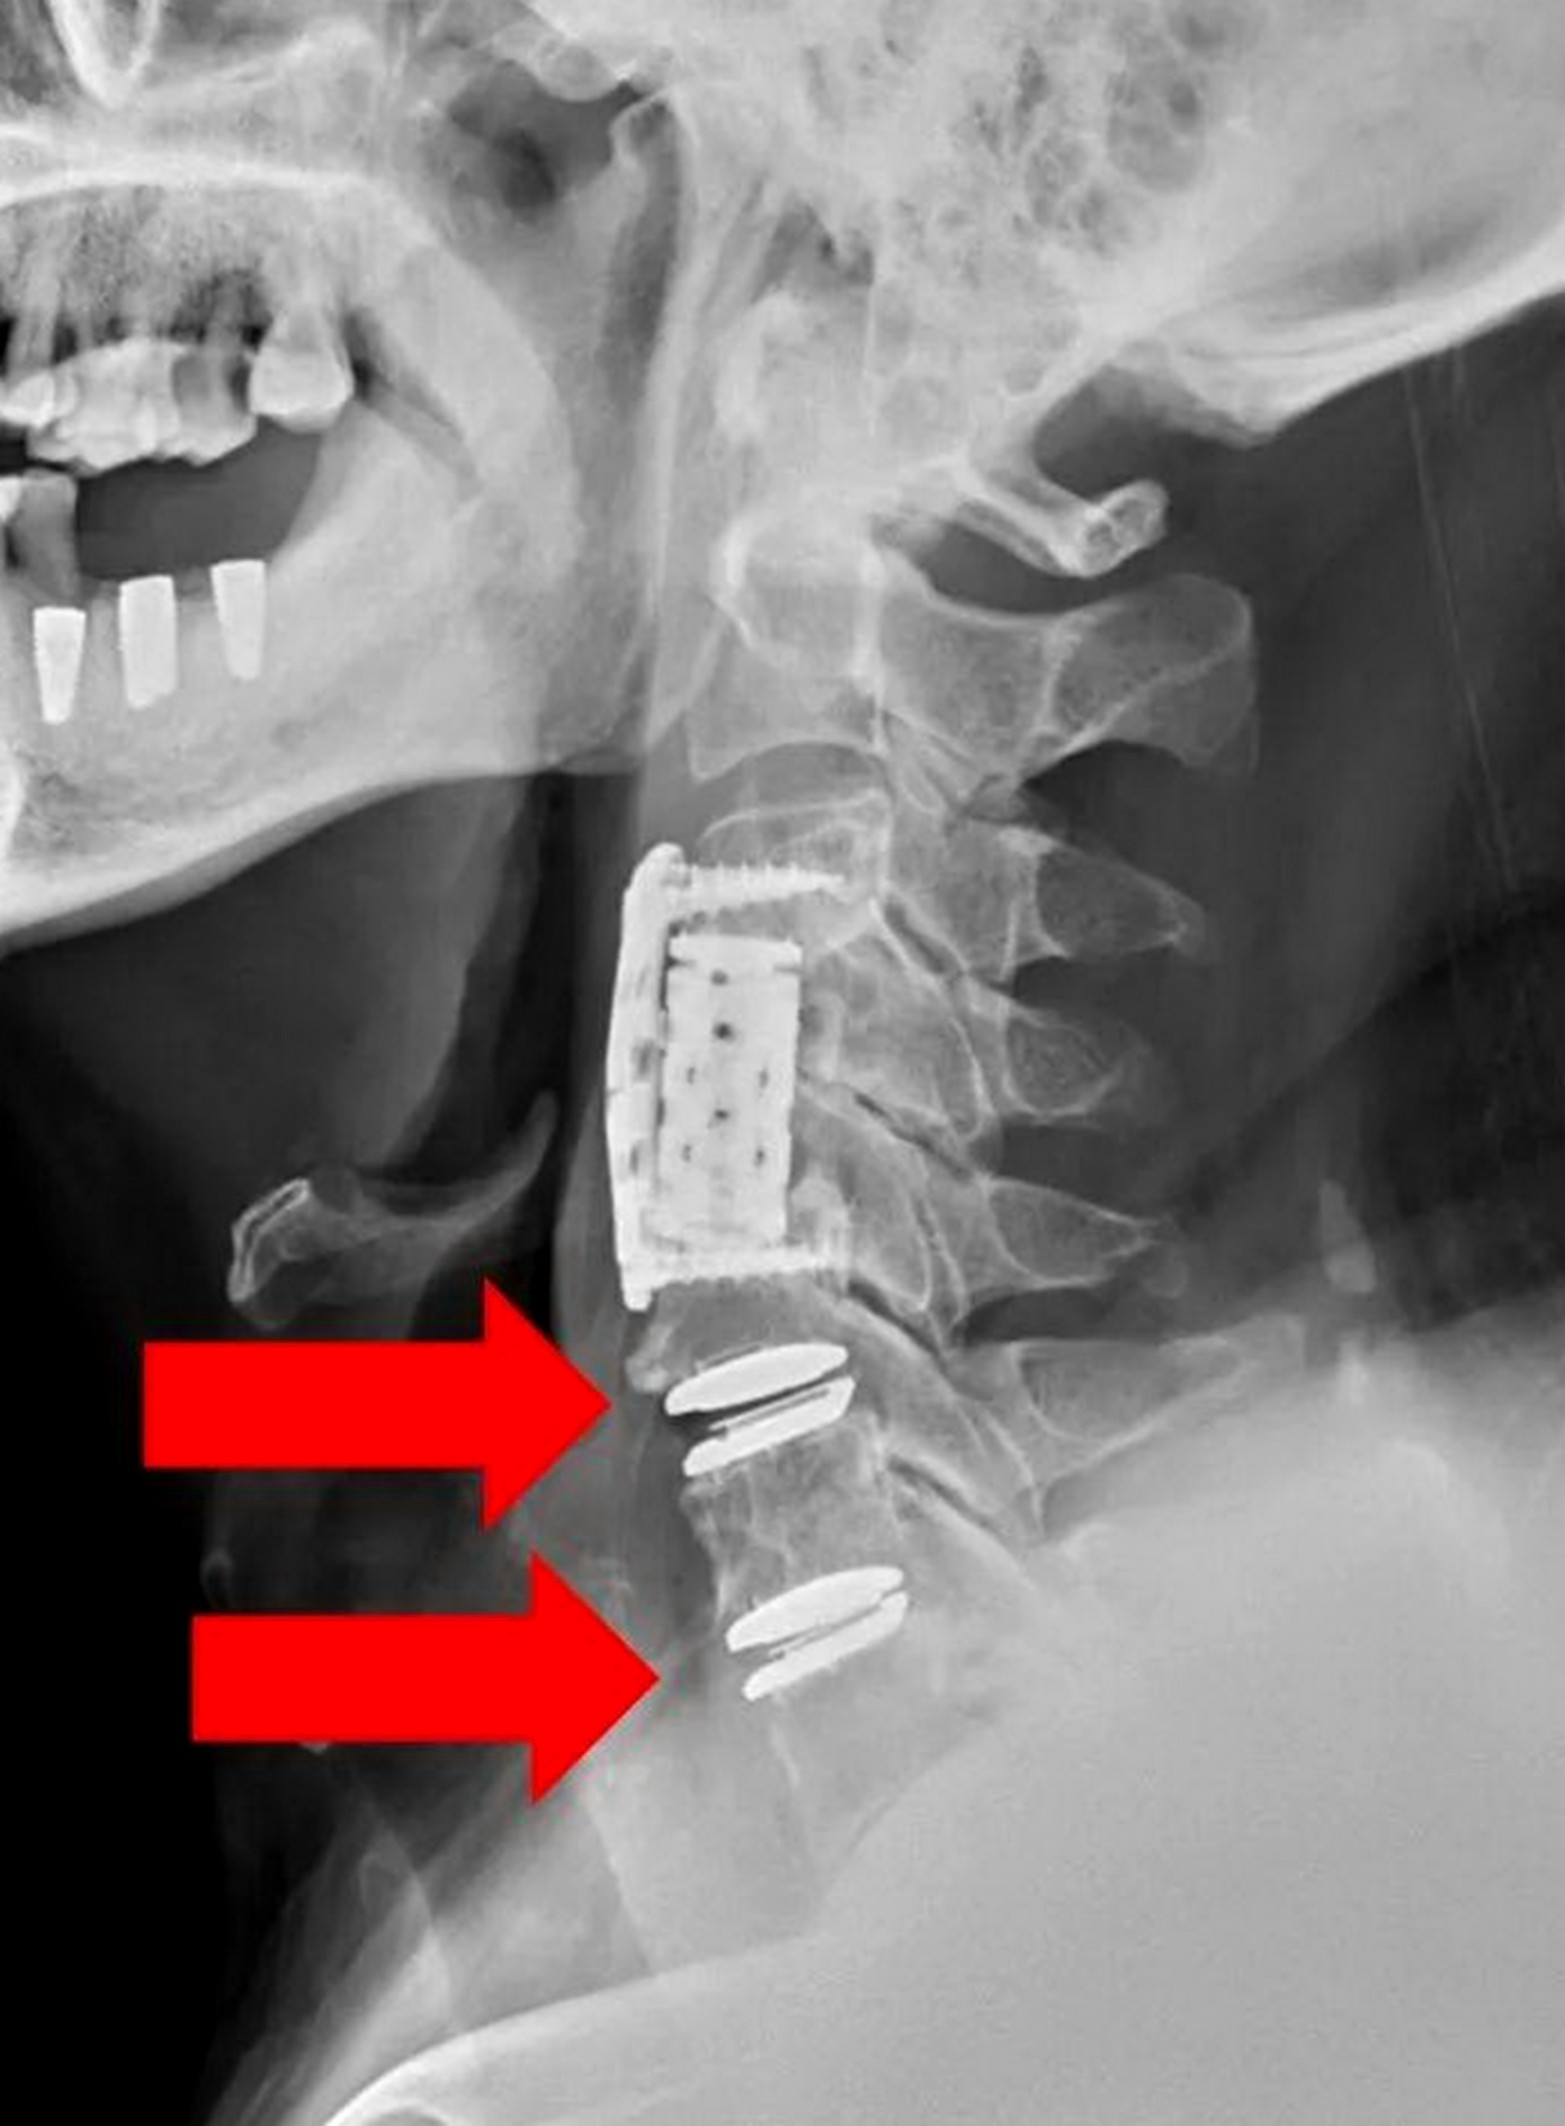

李漢忠說,劉姓台商患有心血管疾病疾,手術複雜度高,加上2次手術,傷口沾黏、脖子相對粗短,也增加手術困難度,這次手術進行第5至第7節頸椎椎間盤切除,及人工椎間盤置換,搭配高規格顯微鏡、導航影像系統及超高速電鑽,大幅降低手術風險,手術歷時約2小時,出血50c.c,術後也不需佩戴頸圈。